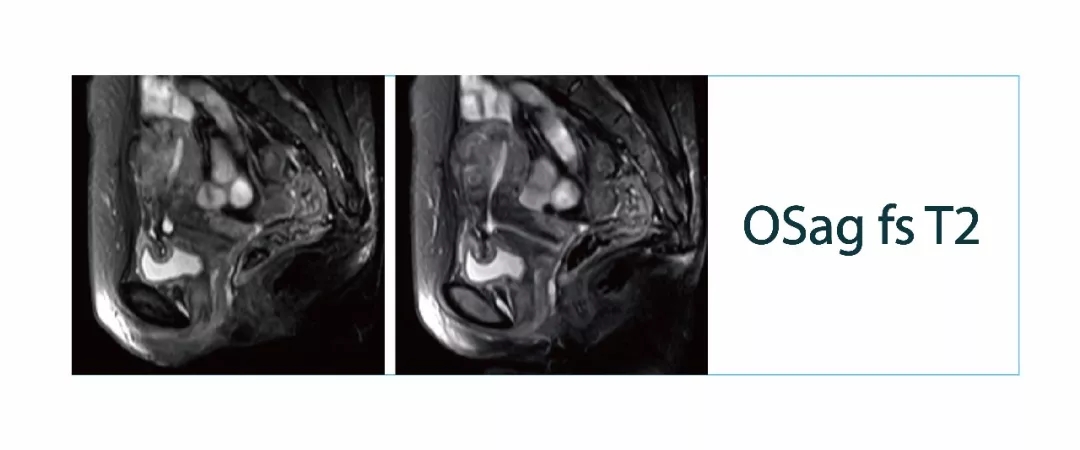

【朗润影像档案】磁共振影像病例分享(编号20180309)